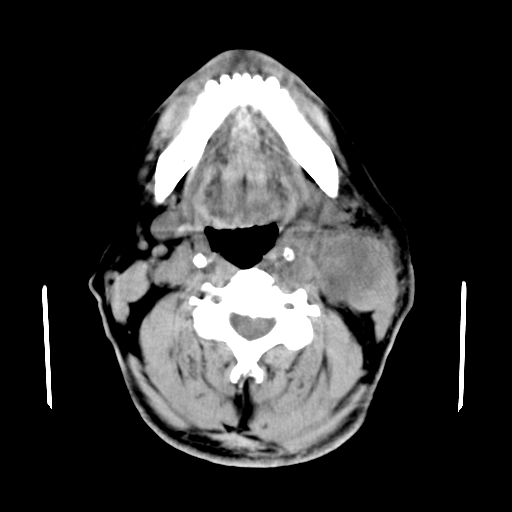

以下是引用卜一在2007-8-6 21:23:00的发言:[br]定位:左侧胸锁乳突肌内侧 颌下腺下后方。特征:弥漫性生长 软组织密度肿块,界限不清,内隐约见低密度坏死。考虑:神经源性肿瘤或血管源性肿瘤。

以下是引用wangzhanshuang在2007-8-6 21:08:00的发言:[br]腮腺混合瘤